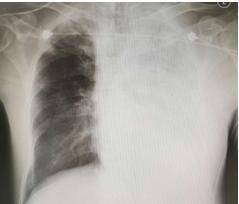

父母便發現女童呼吸狀況變得詭異、越來越喘,醫師當下急照X光檢查,

震驚發現女童「肺部已經白掉大半了」,嘴角甚至流出粉紅色泡泡狀的口水,

這是病毒已經影響女童腦幹的跡象ADVERTISEMENT

女童病情急速惡化,因出現肺部積水緊急轉送加護病房,進行插管、呼吸器治療,